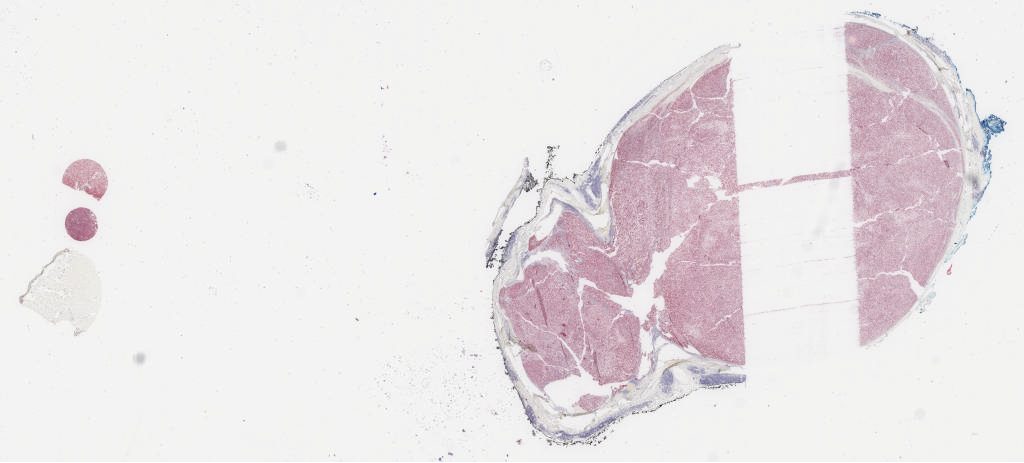

he.svs

85655

x

65015

@

40X